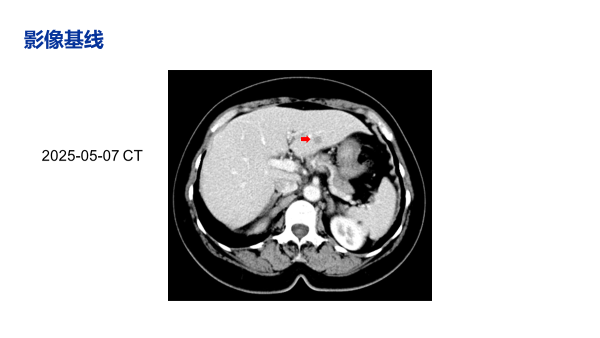

疾病复发:2025年5月,在辅助治疗第13个月,复查B超及CT发现肝左叶新发结节,长径约1.0cm。行肝脏穿刺活检,病理证实为符合乳腺癌来源的转移性腺癌,免疫组化与原发灶一致。

治疗近2个月后(2025-08-04),影像学评估疗效为部分缓解(PR),肝脏转移灶较基线明显缩小。